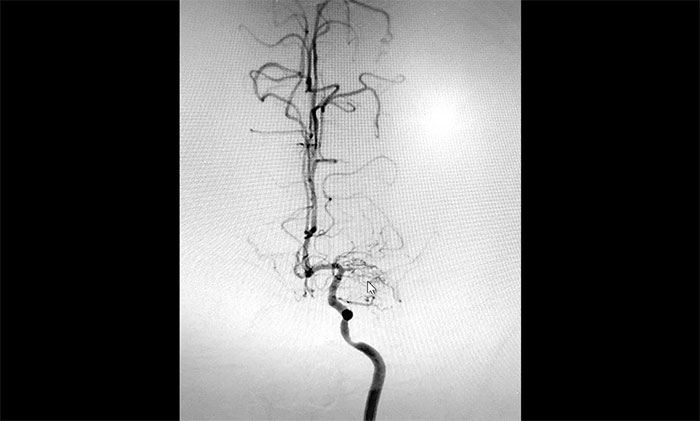

入院后,趙先生的DSA(腦血管造影)檢查再次明確“煙霧病”表現(xiàn):雙側(cè)大腦中動脈主干管腔纖細(xì)、分支細(xì)小;周圍代償性小血管網(wǎng)建立;右側(cè)頸內(nèi)動脈C3-4段纖細(xì),顯影毛糙;兩側(cè)頸內(nèi)動脈C4-6段鈣化形成伴管腔輕—中度狹窄。

▲DSA異常血管造影圖

神經(jīng)外科團(tuán)隊(duì)綜合DSA檢查結(jié)果和患者癥狀表現(xiàn),進(jìn)行了科學(xué)、審慎的評估。于耀宇主任談到,患者雙側(cè)頸內(nèi)動脈虹吸部和大腦中、前動脈主干近段明顯狹窄、近乎閉塞,異常血管網(wǎng)形成。雙側(cè)大腦半球多發(fā)供血區(qū)灌注不足,尤以右側(cè)缺血較為明顯。